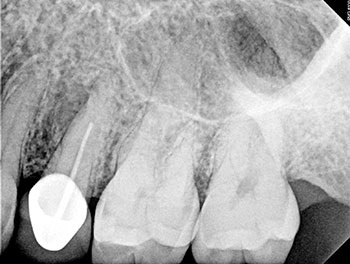

Case 10: Failing ‘well done’ NSRCT

This patient’s teeth #30 and #31 were treated by an endodontist. The endodontist found all the canals, achieved patency and shaped and filled each canal to length. When the periradicular tissues surrounding both teeth failed to heal, the endodontist recommended extracting both teeth because of VRFs. By then, tooth #31 developed a J-shaped lesion, suggestive of a VRF. Nothing suggested that tooth #30 had a VRF, other than that it was a “good-looking” or “well-done” NSRCT that failed. Yet both were recommended for extraction.

The somewhat skeptical patient came to see if these teeth really needed to be extracted. Nonsurgical retreatment was recommended. The patient didn’t want to lose his teeth, but he also didn’t want to pay to re-treat teeth that could not be saved.

Tooth #31—the tooth that was more likely to be fractured—was addressed first. To maximize the likelihood of healing, this tooth was treated in multiple visits using a calcium hydroxide intracanal medicament and obturated after bony healing was complete. The patient was delighted that his tooth had been saved, but also somewhat perplexed that the original endodontist gave up on a tooth that could have been saved. He has now scheduled re-treatment for tooth #30.

More than a few cases have been seen for second opinions after a dentist completed RCT on a tooth that failed shortly after, then told the patient to extract the tooth because it must be cracked because the NSRCT “looked perfect” radiographically. Although shaping and obturation can be judged radiographically, the most important factor—disinfection—cannot.

Endodontic Root Fracture Case Series

Fig.39: Preop CBCT.

Fig.40: Postop PA.

Fig.41: Recall PA.

Fig.42: Recall CBCT.